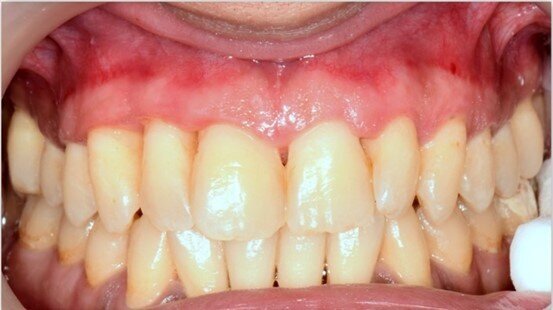

A una settimana dall’applicazione, i pazienti riferiscono una riduzione significativa di sanguinamento e sensibilità gengivale, con risultati superiori rispetto alla sola pulizia professionale. Nei casi di gengivite e tasche parodontali fino a 3 mm, UBIGEL INPERIO ha dimostrato di favorire una parziale o completa regressione dell’infiammazione, contribuendo al ripristino dell’attacco epiteliale e all’eliminazione del sanguinamento grazie alla sua azione antibatterica mirata. Nella Figura 1 è mostrata la situazione iniziale del paziente prima del trattamento.Dopo una settimana dall’applicazione di Ubigel Inperio (Fig. 2), si osservano i primi miglioramenti clinici. Il sondaggio pre-trattamento, effettuato sette giorni dopo l’igiene professionale, evidenziava una profondità di 3 mm con presenza di sanguinamento gengivale (Fig. 3). A distanza di 21 giorni dal trattamento, il sondaggio mostra una profondità della tasca inferiore a 2 mm e l’assenza di sanguinamento, segno di un netto miglioramento dello stato gengivale (Fig. 4).